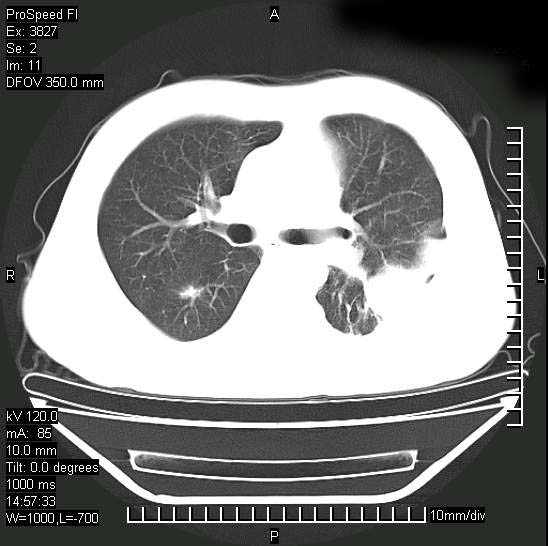

男性,一月前出现右侧肋区疼痛,较剧烈,干咳,无发热,自诉使用抗炎药后缓解,几天前又出现左侧剧烈疼痛,

发热,体温38。9,今天ct,考虑左侧包裹性脓胸,胸腔积液,右上中肺小斑片影,结核/炎症?胸水未见恶性细胞。